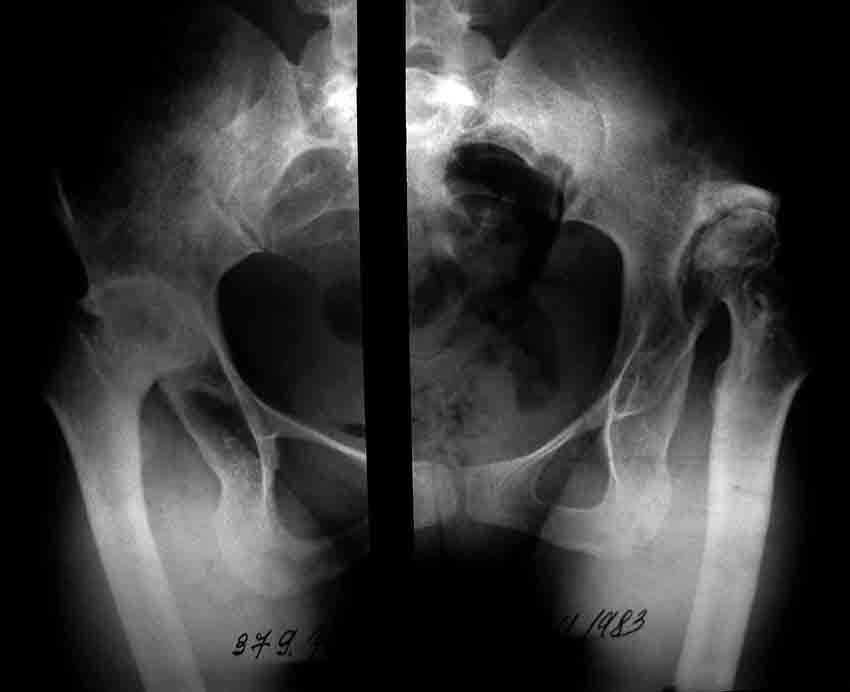

Уважаемые коллеги! Хотелось бы получить совет по тактике лечения. Обратилось 2 девушки - 25 и 26 лет. У обеих грубейшие сгибательные контрактуры тазобедренных суставов.

В одном случае после многократных операций в детстве по поводу врожденных вывихов бедер, в другом - ревматоидный полиартрит. Обе очень маленькие.

Перепробовал все имеющиеся виды шаблонов ножекпротезов - не подходят. На картинке линейка как масштаб - ширина 15мм.